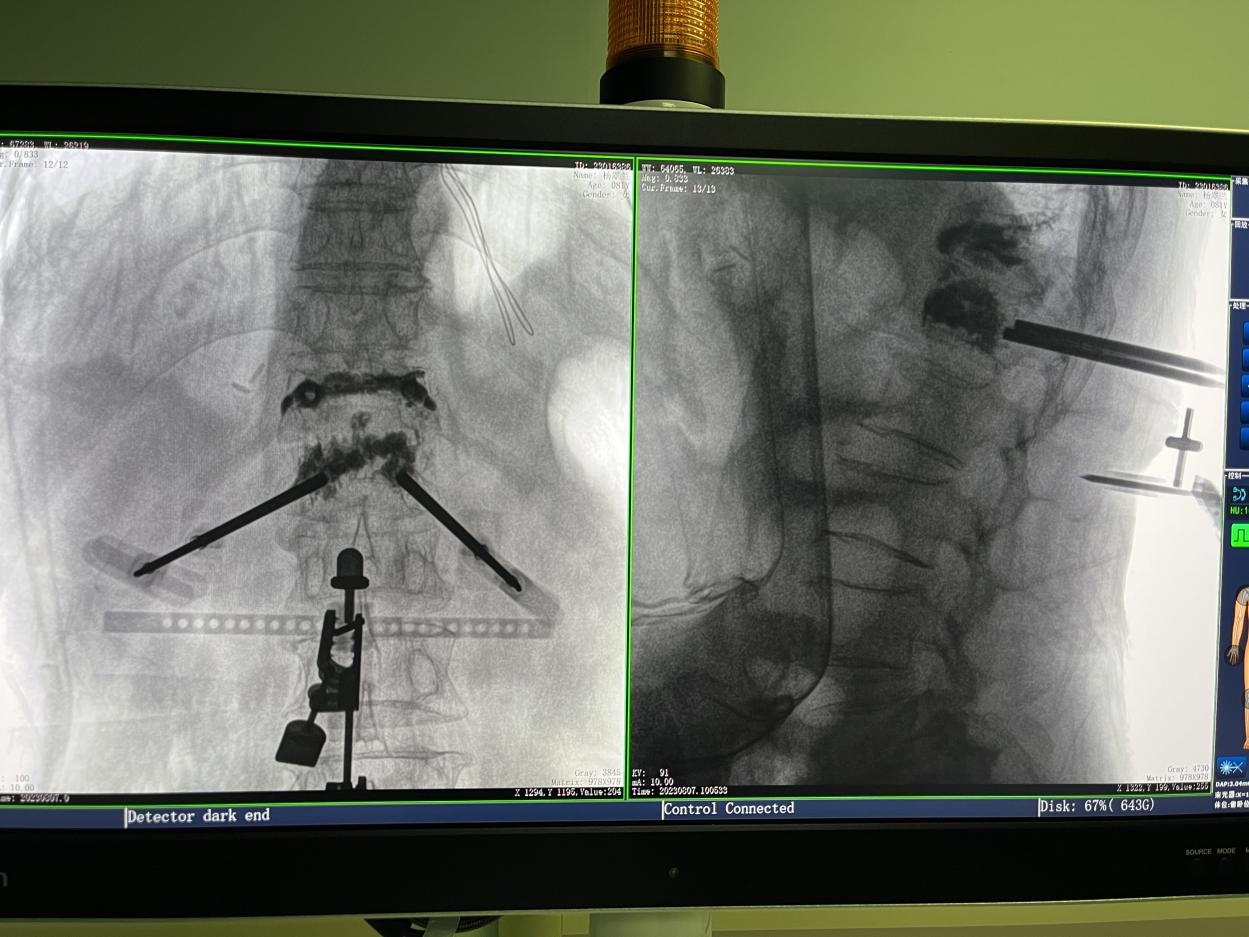

4.微創皮膚切口

傳統的開放式手術需暴露手術可見視野,以便醫生獲得更多的判斷信息,手術創口大,術后恢復時間長。而在骨科機器人輔助的微創手術中,手術創口僅為1~2厘米左右的小切口,創傷小、恢復快。

骨科機器人手術-術后影像